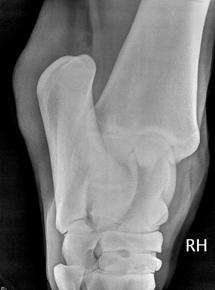

Kulno sąnario OCD (13 pav.) pasireiškia keliose skirtingose sąnario vietose: blauzdikaulio intermedialinėje keteroje, kulno distaliniame lateraliniame skridinyje, rečiau – blauzdikaulio plaktukėliuose ir kulno medialiniame skridinyje (Ross M.W., Dyson S.J., 2003, Bramlage L.R., 2006).

Diagnozuojant ligą, daromos 4 standartinės kulno sąnario rentgenogramos. Tai: dorsoplantarinė, lateromedialinė ir 2 įstrižos projekcijos. Iš jų dorsolateralinė ar dorsoplantarinė mediolateralinė įstrižos projekcijos suteikia daugiausiai informacijos (Ross M.W., Dyson S., 2003, Bramlage L.R., 2006).

13 pav. a) Medialinė įstriža kulnakaulio projekcija. b) Lateralinė kulnakaulio projekcija (cal.vet.upenn.edu ).